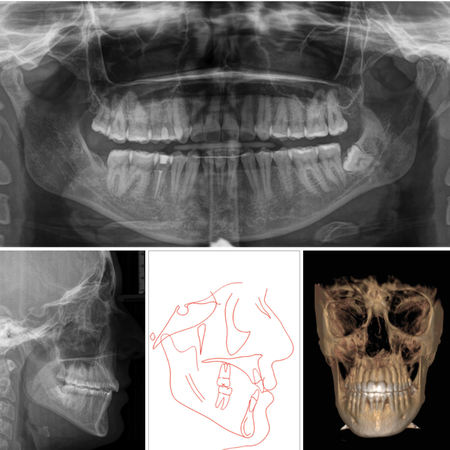

Tratamento ortodôntico-cirúrgico de má oclusão de Classe II esquelética usando alinhadores

OBJETIVO: Relatar o caso clínico de um paciente com má oclusão de Classe II esquelética e dentária, com queixa principal inicial de roncopatia e queixa secundária sobre o perfil e a estética facial (sorriso). RELATO DO CASO: De posse dos elementos diagnósticos, avaliação clínica e facial, optou-se por um tratamento ortodôntico-cirúrgico. Após elaboração do plano digital (ClinCheck®, Align Technology) e recebimento da sequência de 67 alinhadores, seguiu-se com distalização...